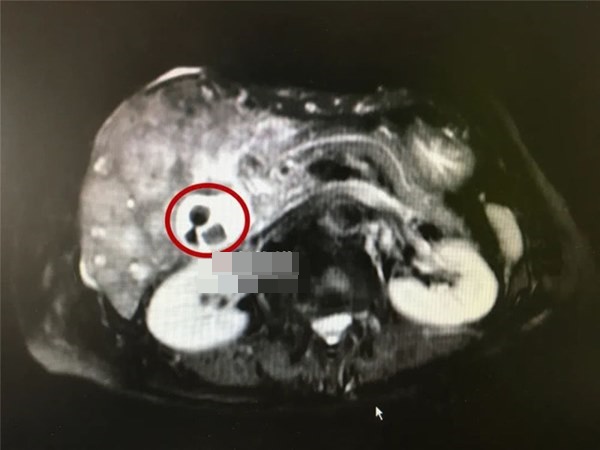

Sau khi hiểu tình hình của bà, bác sĩ liền nhanh chóng sắp xếp để chụp MRI gan cùng các chỉ số khối u cho bà. Trong quá trình kiểm tra, bác sĩ phải "giật mình" khi thấy bà Chu đang ở giai đoạn cuối của ung thư túi mật, các tế bào khối u gần như đã ăn mòn toàn bộ gan của bà!

Những viên sỏi mật này đã ở trong cơ thể bà Chu ít nhất 40 năm và gây nên ung thư túi mật giai đoạn cuối.

Theo ông Zhu Danyang – bác sĩ chuyên khoa phẫu thuật ung thư tại bệnh viện Y học Trung Quốc cho biết, do khối u làm tắc ống dẫn mật nên làm da bà Chu ngả vàng nặng. Chưa hết, trong quá trình chụp MRI gan, ông đã phát hiện ra có hơn 10 viên sỏi nhỏ có đường kính 0,5mm trong túi mật. Theo tiền sử dịch tễ, ắt hẳn chúng đã ở trong cơ thể bà ít nhất 40 năm.